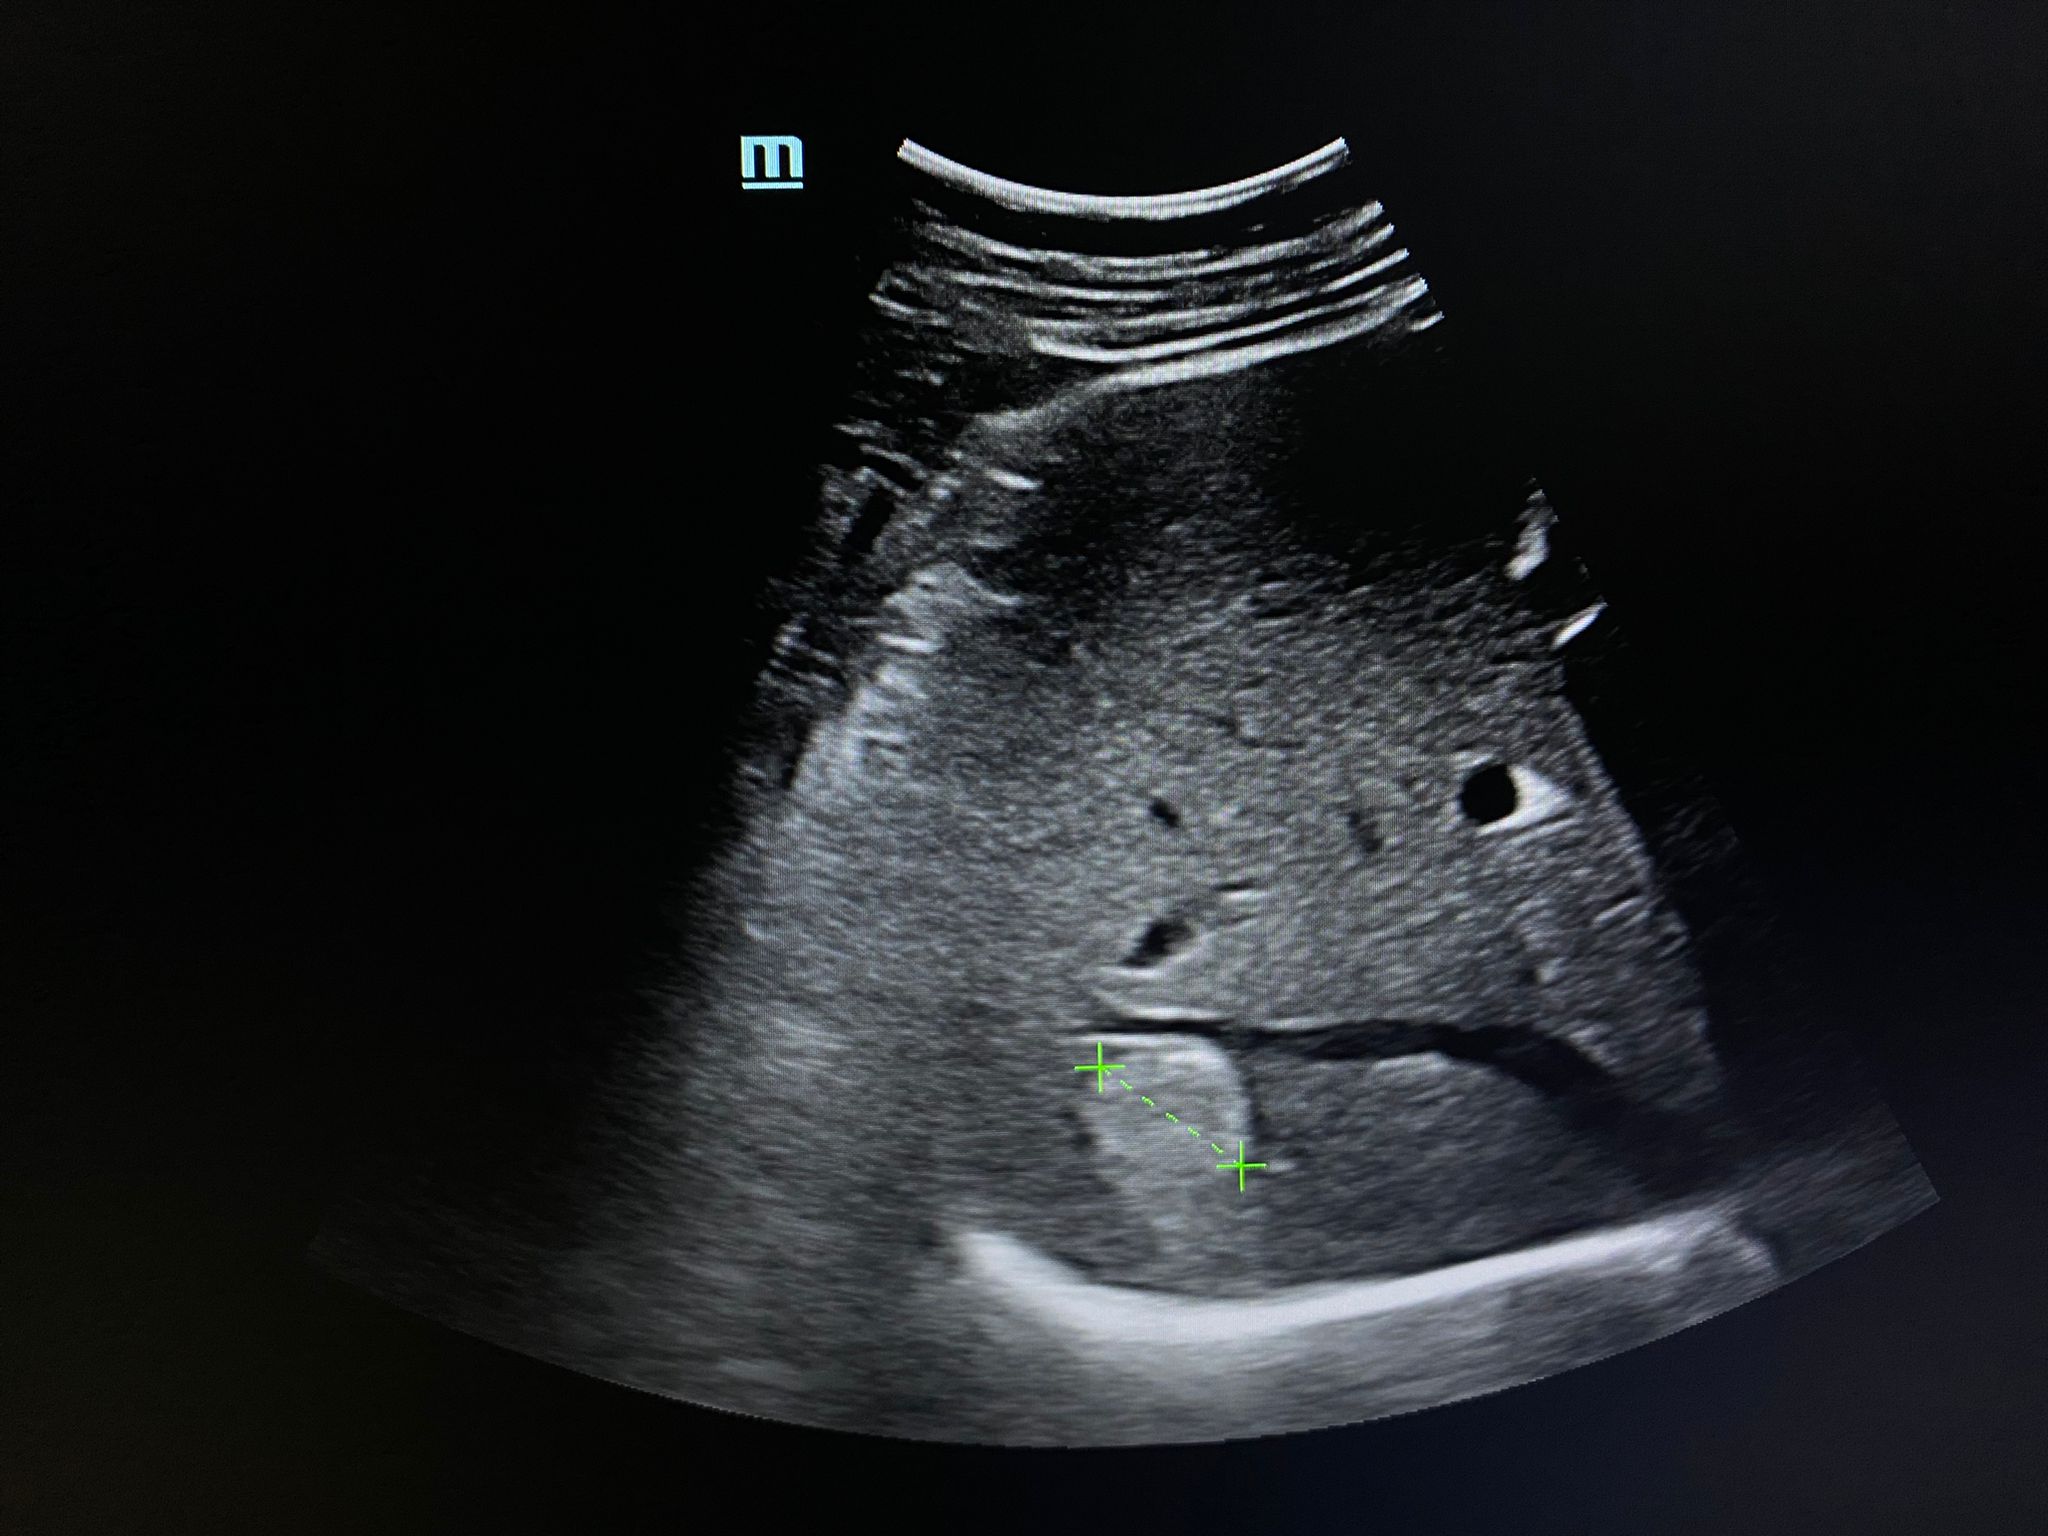

Como hallazgos, se aprecia un aumento moderado y difuso de la ecogenicidad hepática, ya descrito en ecografías previas, además de algunas áreas más hipoecoicas de límites geográficos en cara anterior de la bifurcación portal que pudieran corresponder a zonas de parénquima libre de grasa. Pero además, en el lóbulo hepático derecho, se aprecia una LOE solitaria hiperecogénica, de bordes irregulares, bien delimitada, con un halo hipoecoico y con registro Doppler negativo.